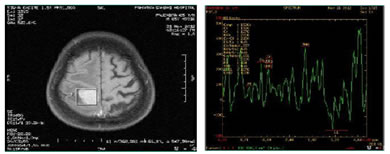

Figure 3: 45 yr old lady with Medulloblastoma in posterior fossa showing taurine peak at 3.4 ppm